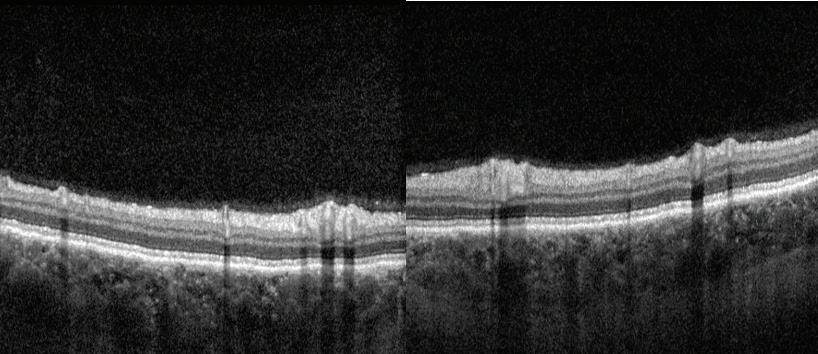

From a campus culture standpoint, the lowest preintervention question scored was verbal or physical abuse by other students, faculty, and personnel.

Table 1. Medical Student Stressor Questionnaire Results

While slight increases occurred post-intervention, they were still all below 1. Increases may have been due to poorly perceived interactions during rotations and/or variability amongst participants completing the surveys. Overall, these low scores indicate that the campus emphasized student safety during this year. The Guthrie campus offers student support from campus-specific faculty as well as from overarching school faculty in case of any abusive behavior.

The authors feel the events provided, while not showing statistical significance, still had an individuallevel impact. By organizing the events, students were provided a carved-out time where they could actively focus on wellness, connecting with other students and the local community. Wellness is a dynamic process, that can change both short term and long term. As such, wellness may have increased during the events themselves, and fluctuated afterwards depending on social, emotional, and academic influences. The lack of statistical significance could be attributed to the low sample size. Prior work has shown that other interventions, such as yoga, also had a positive effect on student wellness, further supporting the implementation of wellness activities (20).